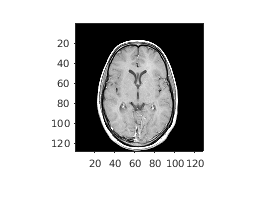

Считайте 3-D объем в рабочую область. Это изображение состоит из 27 систем координат 128 128 пиксельных изображений.

load mri;

D = squeeze(D);

D = ind2gray(D,map);

Создайте imref3d пространственный объект привязки сопоставлен с объемом. В иллюстративных целях обеспечьте пиксельное разрешение в каждой размерности. Разрешение находится в миллиметрах на пиксель.

R = imref3d(size(D),2,2,4)

R =

imref3d with properties:

XWorldLimits: [1 257]

YWorldLimits: [1 257]

ZWorldLimits: [2 110]

ImageSize: [128 128 27]

PixelExtentInWorldX: 2

PixelExtentInWorldY: 2

PixelExtentInWorldZ: 4

ImageExtentInWorldX: 256

ImageExtentInWorldY: 256

ImageExtentInWorldZ: 108

XIntrinsicLimits: [0.5000 128.5000]

YIntrinsicLimits: [0.5000 128.5000]

ZIntrinsicLimits: [0.5000 27.5000]

Отобразите средний срез объема, не использовав пространственный объект привязки. Координаты осей отражают внутренние координаты. Заметьте, что координата (0,0) находится в левом верхнем углу этой плоскости. z=0 является правильным ниже первого среза, и ось z положительна в восходящем направлении к короне головы.

figure

imshow(D(:,:,13))

axis on

Figure contains an axes object. The axes object contains an object of type image.

Предположим, что вы хотите определить положение, в миллиметрах, функций в этом срезе. Выберите четыре точки выборки и сохраните их внутренние координаты в векторах. Например, первая точка имеет внутренние координаты (54,46,13). Внутренняя z-координата является тем же самым для всех точек в этом срезе.

xI = [54 71 57 70];

yI = [46 48 79 80];

zI = [13 13 13 13];

Преобразуйте внутренние координаты в мировые координаты с помощью intrinsicToWorld.

[xW,yW,zW] = intrinsicToWorld(R,xI,yI,zI)

xW = 1×4

108   142   114   140

yW = 1×4

92    96   158   160

zW = 1×4

52    52    52    52

Итоговые векторы являются миром x-, y-, и z-координатами, в миллиметрах, выбранных точек. Первая точка, например, возмещена от источника на 108 мм в направлении X, 92 мм в направлении Y и 52 мм в z-направлении.